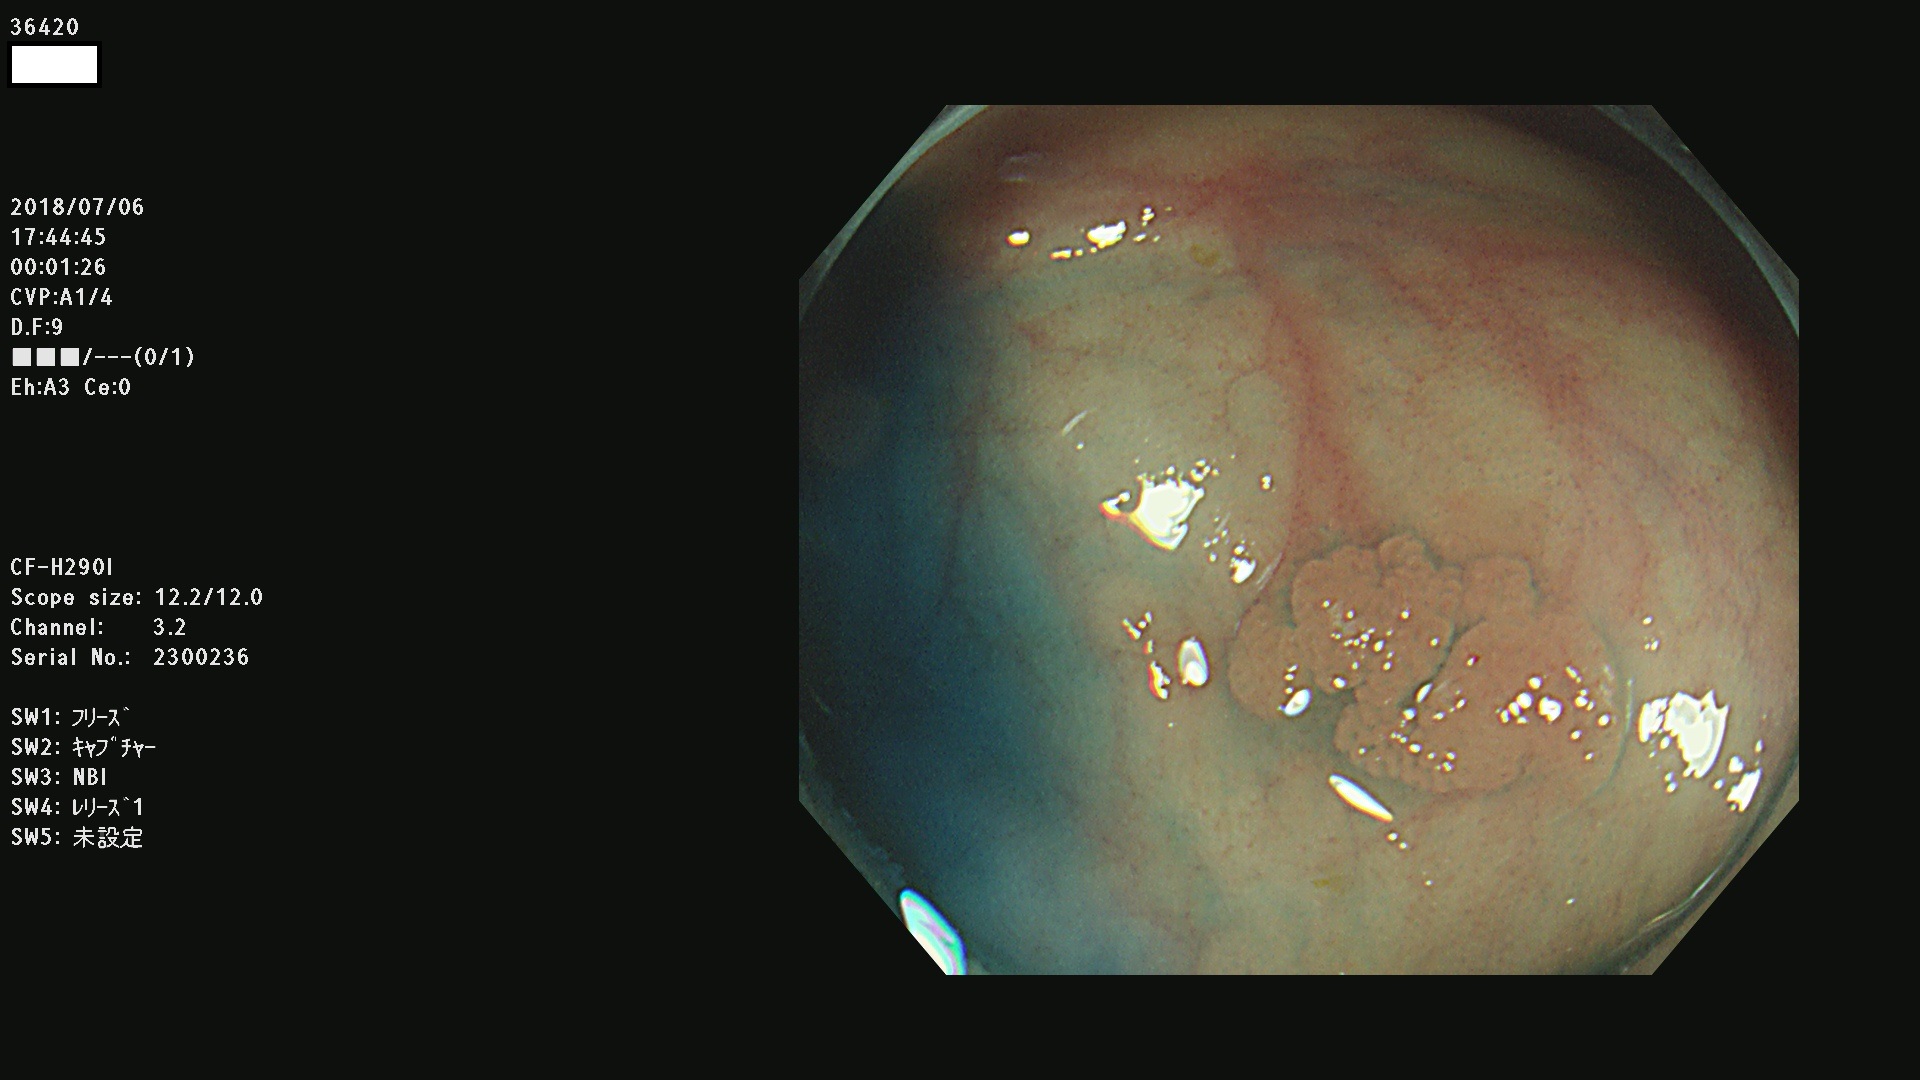

36400(SSAPのみ) 36402 36403 36404 36405 36406 36407 36408(SSAPのみ) 36412 36413 36414 36415 36416 36417 36418 36420 36422 36423 36424 36425 36426 36428 36429 36430 36431 36434 36435 36436 36437 36438 36440 36443 36447 36448 36449 36450 36452 36454 36458 36459 36460 36462(SSAPのみ) 36463 36464 36465 36466 36470 36471 36472 36473 36474 36475 36476 36478 36480 36481 36482 36484 36487 36488 36489 36490 36492 36494 36495 36496 36497 36498

発見困難で危険性の高い平坦型病変(上記100名より抽出)